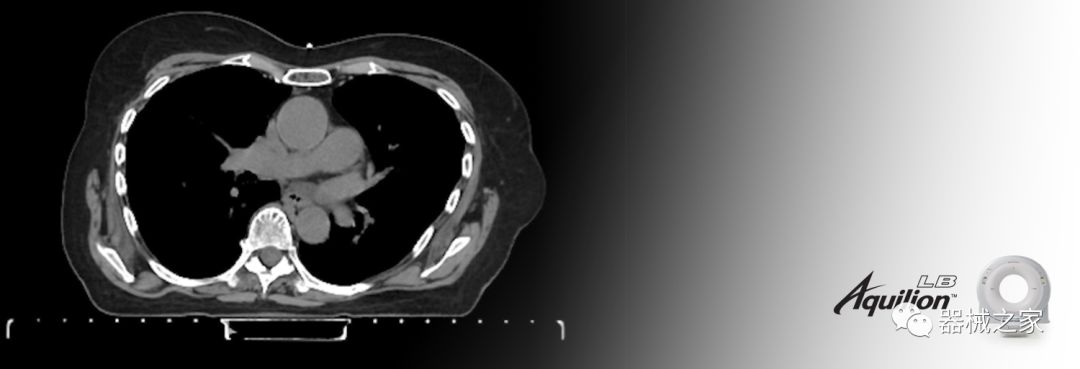

在以患者為中心的放射腫瘤學(xué)領(lǐng)域,計(jì)算機(jī)斷層掃描(CT)的可訪問(wèn)性,可重復(fù)性和靈活性至關(guān)重要。為了建立這些價(jià)值,佳能醫(yī)療系統(tǒng)美國(guó)公司現(xiàn)在正在擴(kuò)大其放射腫瘤學(xué)CT模擬產(chǎn)品,包括Aquilion Prime SP和Aquilion Lightning 80高級(jí)CT系統(tǒng)。除了Aquilion LB之外,Aquilion Prime SP和Aquilion Lightning 80現(xiàn)在還包括放射治療(RT)選項(xiàng),可為腫瘤學(xué)規(guī)劃提供高質(zhì)量的CT成像和精密工具。

佳能醫(yī)療的Aquilion Lightning 80掃描儀還以緊湊,經(jīng)濟(jì)的包裝提供高質(zhì)量的成像。Aquilion Lightning 80旨在可靠,高效地運(yùn)行,在繁忙的環(huán)境中生成高質(zhì)量的圖像。

Aquilion LB專為滿足腫瘤學(xué)挑戰(zhàn)而設(shè)計(jì),同時(shí)優(yōu)先考慮患者護(hù)理。Aquilion LB的內(nèi)徑為90 cm,能夠幫助復(fù)雜的患者設(shè)置并提高患者的舒適度。CT模擬定位可以輕松鏡像放射治療定位,更加自信。該系統(tǒng)采用0.5 mm x 16排(32層)PUREViSION探測(cè)器技術(shù),70 cm視野,AIDR 3D和SEMAR技術(shù)。